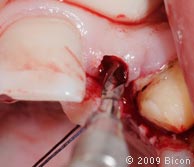

5. Ретракционные швы, удерживающие два небных лоскута.

6. Пилотная остеотомия верхнего правого бокового резца 2.0мм бором на 1100 RPM с внешним орошением.

7. Пилотная остеотомия верхнего левого бокового резца 2.0мм бором на 1100 RPM с внешним орошением.